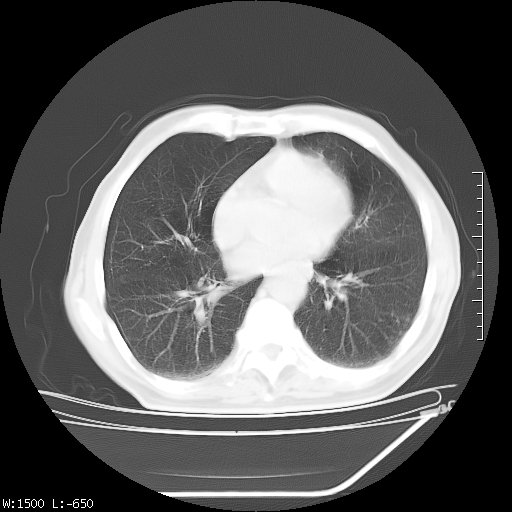

标题: CT23994:男、72、咳嗽、气短两月余,近来消瘦。 [打印本页]

标题: CT23994:男、72、咳嗽、气短两月余,近来消瘦。

右上肺实变,与胸膜关系密切,右肺容积缩小,隆突下淋巴结增大,考虑1 肺结核 2 肺癌

右上肺大片状密度增高影,与胸膜关系密切,内见低密度透亮影,胸膜下可见三角形不张影,左下肺沿支气管走形结节影,纵膈内淋巴结显示。考虑结核并疤痕性不张可能性大,建议穿刺活检,排除肺泡癌。